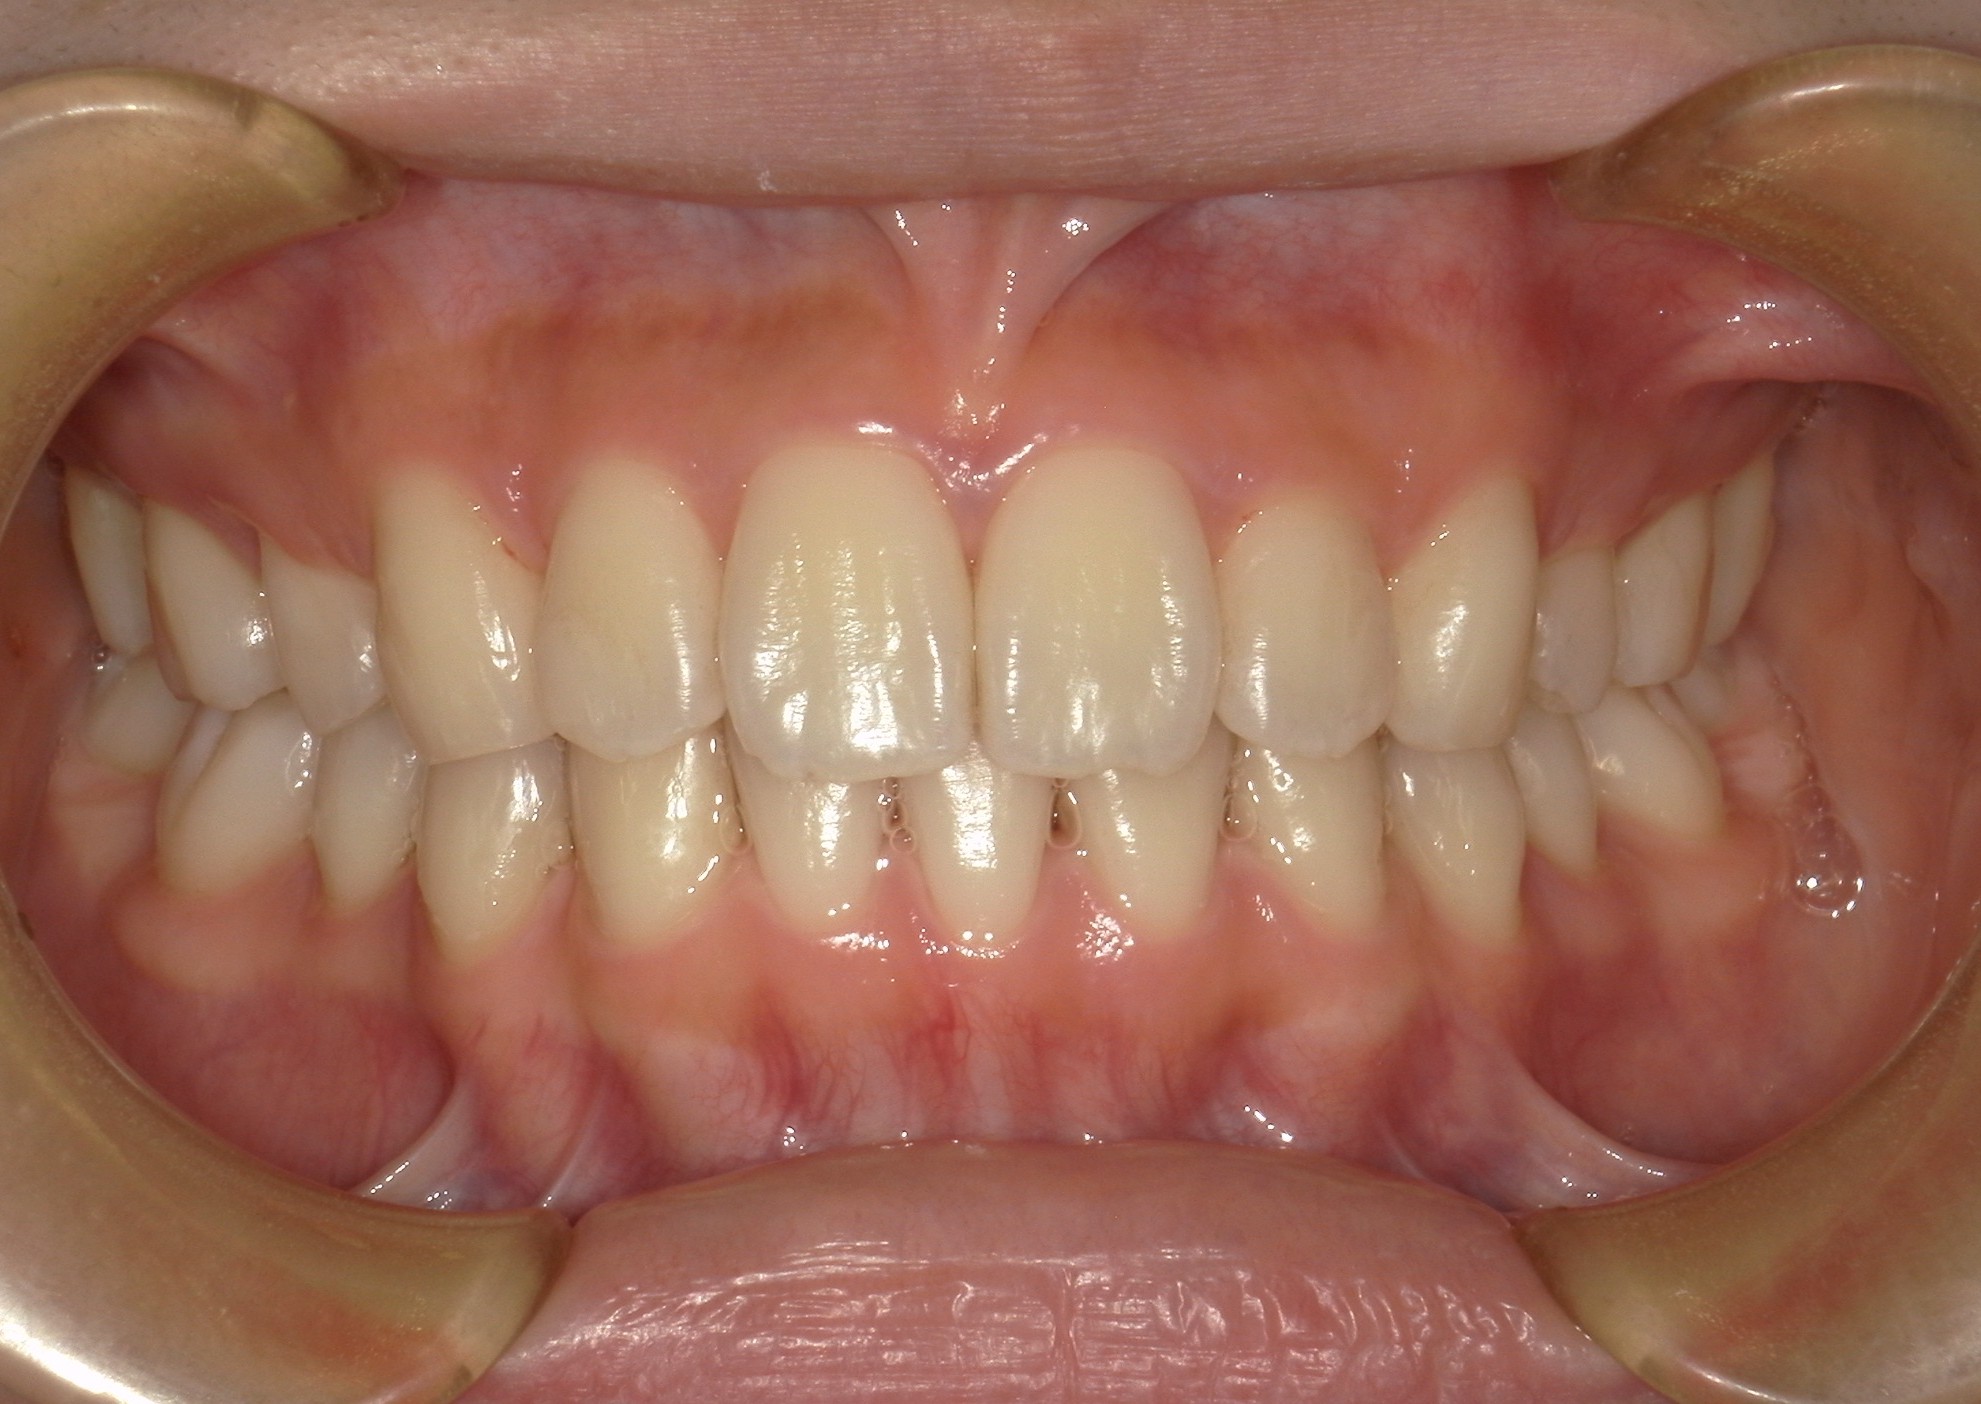

口内正面

治療前

治療後

横から見た口腔内写真でよくわかるように、前歯が出っ歯になっており、全く咬んでいない状態でした。また下の前歯が本来4本あるところが、先天的に一本少なく3本しかない(Three incisors)であったため下顎のアーチが小さいというお口の状態でした。前歯を正しい傾きに治し、咬合させるため、上の歯のみ2本の抜歯を行うこととしました。下の前歯が3本のため、その正中に注意しながら前歯の傾きを修正し、奥歯のポジションを整えて仕上げました。口元の突出感は大きく改善し、咬合も良好な状態で完了することができました。